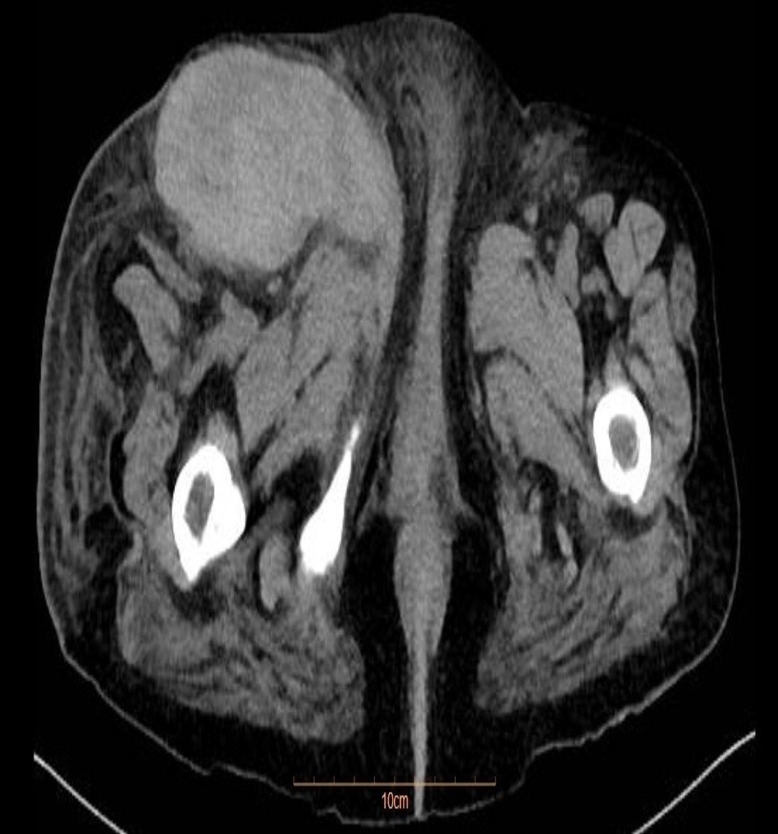

Case presentation: A 64-year-old female with a history of chronic endocarditis and valvular involvement underwent femoral coronary angiography as part of her cardiac evaluation. On the first postoperative day, the patient developed worsening pain, swelling, and redness in her right lower extremity, which worsened despite antibiotic therapy and pain management. The patient was diagnosed with necrotizing fasciitis. An emergent right lower extremity fasciotomy was performed to debride the necrotic tissue and release the tension caused by acute compartment syndrome.